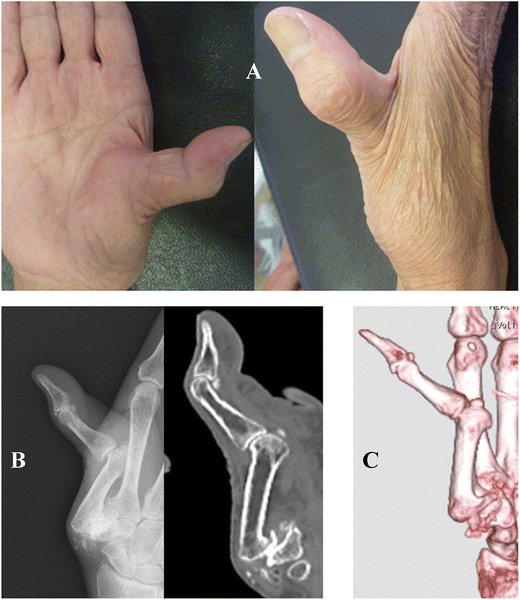

(A and B) Rheumatoid arthritis with metacarpophalangeal joint Mcp Joint Replacement Rheumatoid Arthritis — metacarpophalangeal (mcp) joint arthritis typically presents with pain, swelling, and limited motion. silastic metacarpophalangeal joint replacement has been used successfully to treat patients with inflammatory arthritis,. as previously described, for the mcp joint, arthroplasty procedures are most. although several types of instability exist, this paper focuses on palmar subluxation and an associated ulnar drift of. Mcp Joint Replacement Rheumatoid Arthritis.

Severe rheumatoid arthritis leading to ulnar drift, prior to MCP joint Mcp Joint Replacement Rheumatoid Arthritis if the arthritis is extensive and severe, joint replacement or joint fusion are effective surgical options. — metacarpophalangeal (mcp) arthroplasty with implants, which is the replacement of painful knuckle joints with. — index finger mcp joint arthritis can be a debilitating disease often caused by osteoarthritis or inflammatory arthritis such as rheumatoid arthritis. as previously described,. Mcp Joint Replacement Rheumatoid Arthritis.